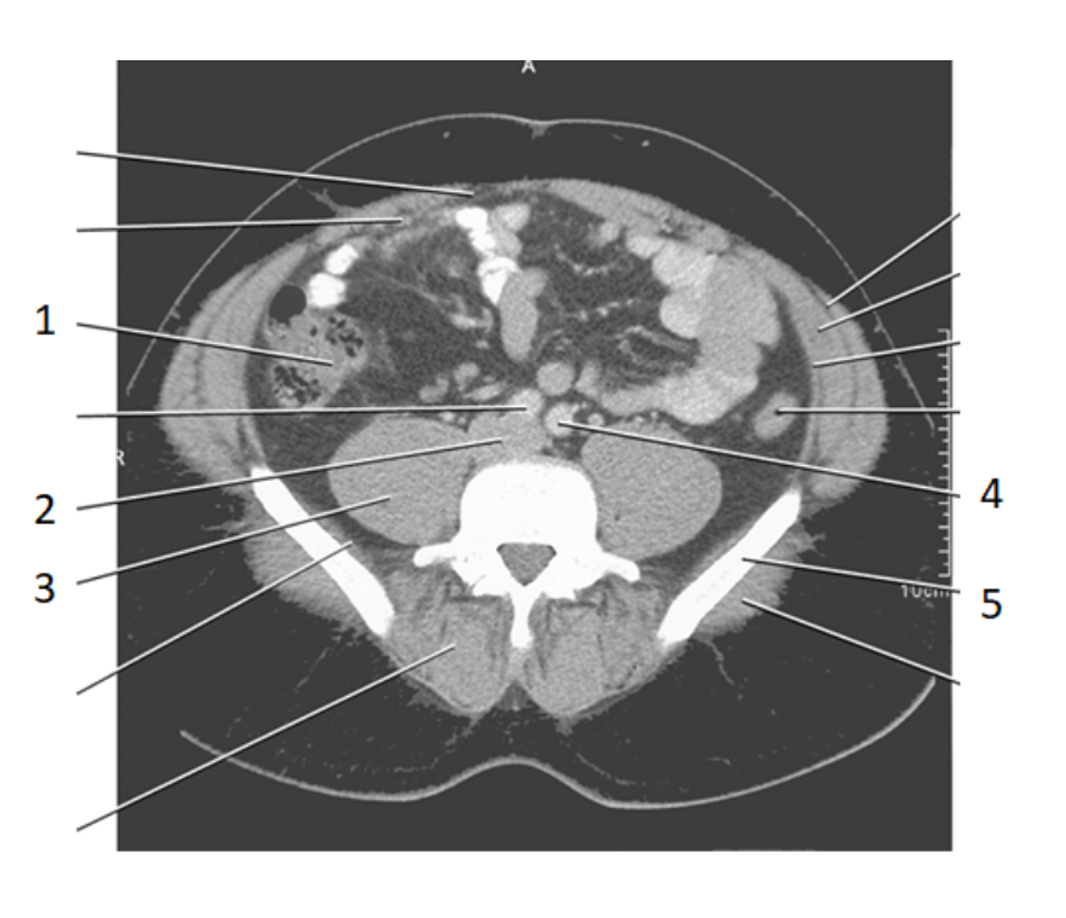

2

aorta

4

left common iliac artery

3

ureters

8

psoas

24

kidney

14

20

small bowel

21

large bowel